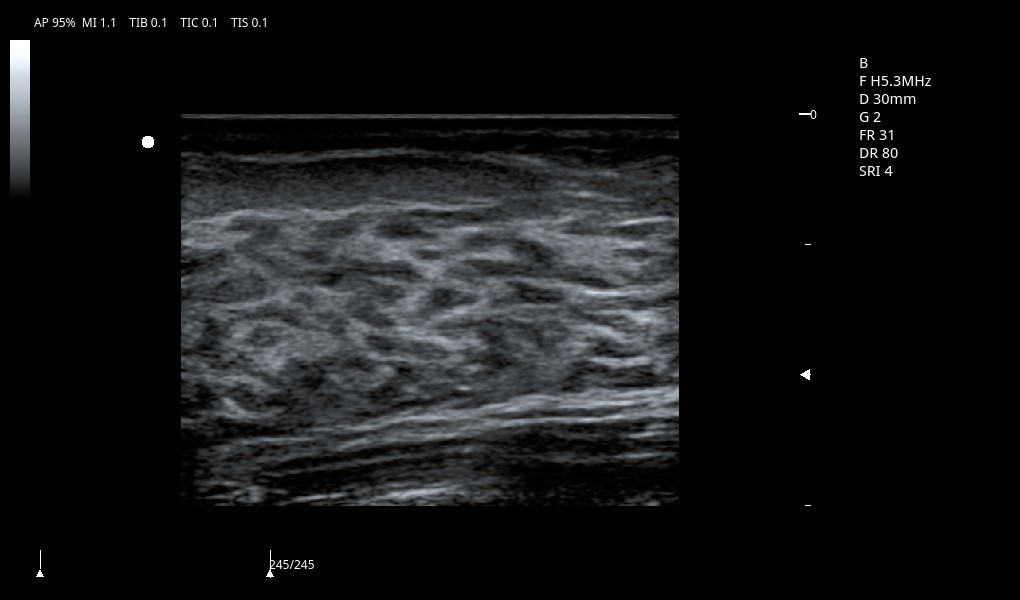

Excelentes imágenes clínicas

|

|

|

|

|

|